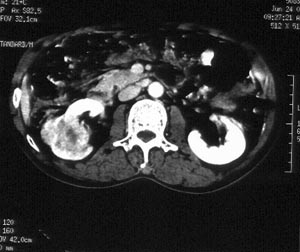

男性,56岁。右腰部不适2月。无血尿,无尿频尿急尿痛。b超提示:右肾下极占位。

ct平扫加增强扫描:右肾中下极肾盂外侧段实质见分叶状软组织密度肿块,截面大约56x45mm,向外突破肾包膜,向内突入肾盂,平扫密度略不均,ct值32-37hu。c+见病灶不均匀轻-中度强化,内有未强化坏死区。右侧肾周筋膜增厚,右肾内前方见肿大淋巴结。

ct诊断:右肾癌,ct表现见上述,伴同侧腹膜后淋巴结转移。

手术所见:右肾大小15x7cm,背侧有肿物突出肾包膜,大小7x4cm。行“右肾癌根治术”。

手术病理:

透明细胞癌(ⅰ-ⅱ级)